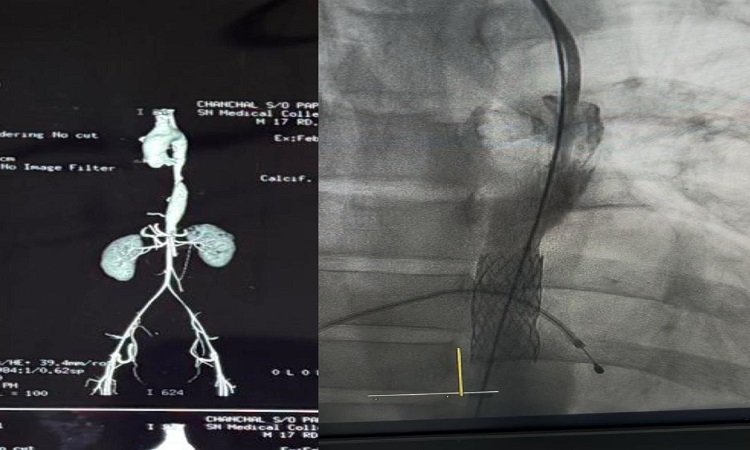

SNMC Agra: उत्तर प्रदेश के आगरा में एसएन मेडिकल कॉलेज के सुपर स्पेशियलिटी के कॉर्डियोलॉजी विभाग ने एक किशोर को नई जिंदगी दी है. 17 वर्षीय किशोर लंबे समय से हृदय की मुख्य धमनी (एओर्टा) में आई अत्यंत गंभीर रुकावट की वजह से परेशानी जूझ रहा था. जब एसएन मेडिकलज कॉलेज आया तो एसएनएमसी के कार्डियोलॉजिस्ट डॉ. हिमांशु यादव ने किशोर की हृदय की मुख्य धमनी (एओर्टा) में आई अत्यंत गंभीर रुकावट को स्टेंटिंग के जरिए सफलतापूर्वक ठीक किया है. इस तरह की सर्जरी आगरा और आसपास के समूचे क्षेत्र में पहला सफल केस है.

एसएनएमसी के कार्डियोलॉजिस्ट डॉ. हिमांशु यादव ने बताया कि 17 वर्षीय मरीज पिछले काफी समय से ‘रेसिस्टेंट हाइपरटेंशन’ से पीड़ित था. जिसकी वजह से मरीज का ब्लड प्रेशर (BP) ऊपर के अंगों में 240/120 तक पहुंच जाता था. जबकि पैरों में बीपी रिकॉर्ड ही नहीं हो पाता था. इस गंभीर स्थिति के कारण महज 17 साल की उम्र में उसे 3 माह पहले ब्रेन हैमरेज (इन्ट्रारेब्रल हैमरेज) भी हो चुका था.

मेडिसिन विभाग के डॉ. शिवांग शर्मा और डॉ. हरि सिंह ने गहन जांच के बाद मरीज को ‘कोआर्कटेशन ऑफ एओर्टा’ (Coarctation of Aorta) से ग्रसित पाया. जिसमें ही उसकी मुख्य धमनी में लगभग 99% तक रुकावट थी. जो बाल के बराबर पतली रह गई थी. दो सप्ताह की विस्तृत योजना और होमवर्क के बाद कॉडियोलिस्ट डॉ. हिमांशु यादव ने बिना किसी बाहरी विशेषज्ञ की मदद के स्वयं इस जटिल स्टेंटिंग प्रक्रिया को सफलतापूर्वक अंजाम दिया. ऑपरेशन के बाद अब धमनी में रक्त का प्रवाह पूरी तरह सामान्य है और मरीज स्वस्थ है. इस सफल प्रक्रिया में डॉ. हिमांशु यादव, डॉ. शिवांग शर्मा, डॉ. हरि सिंह और उनकी पूरी टीम का विशेष योगदान रहा.